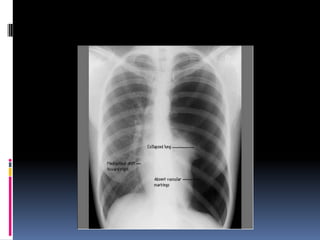

Heart

   Size

   Shape

   Silhouette-margins should be sharp

   Diameter (>1/2 thoracic diameter is

enlarged heart)

 AP views make heart appear larger than it

actually is.

Costo-phrenic / cardiophrenic angles

Margins should

be sharp

Heart  Size  Shape  Silhouette-margins should be sharp  Diameter (>1/2 thoracic diameter is enlarged heart)  AP views make heart appear larger than it actually is.